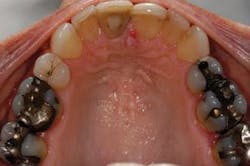

For instance, many patients, when given the option, may prefer to combine both immediate-need treatment with future-need treatment. Advantages of this approach include decreased chair time and fewer visits, impressions, and injections (Fig 4). From a restorative standpoint, we can often better manage the occlusion and blending of restorative materials for an optimal result when the dentistry is approached in a more integrated way.

For patients to proceed with treatment in a comprehensive way, they must feel confident in our ability to deliver care. There are multiple methods of demonstrating capability to patients — clean and tidy offices, pleasant, long-term staff members, and patient testimonials. However, I have found that sharing photographs of restored arches that demonstrate the transformations possible with modern materials and techniques is very effective (Figs. 5 and 6; 7 and 8). Just as everyone appreciates how restorative dentistry can improve a person’s smile, patients also appreciate how posterior dentistry can improve a deteriorating situation — especially when the preoperative case reflects their own needs.